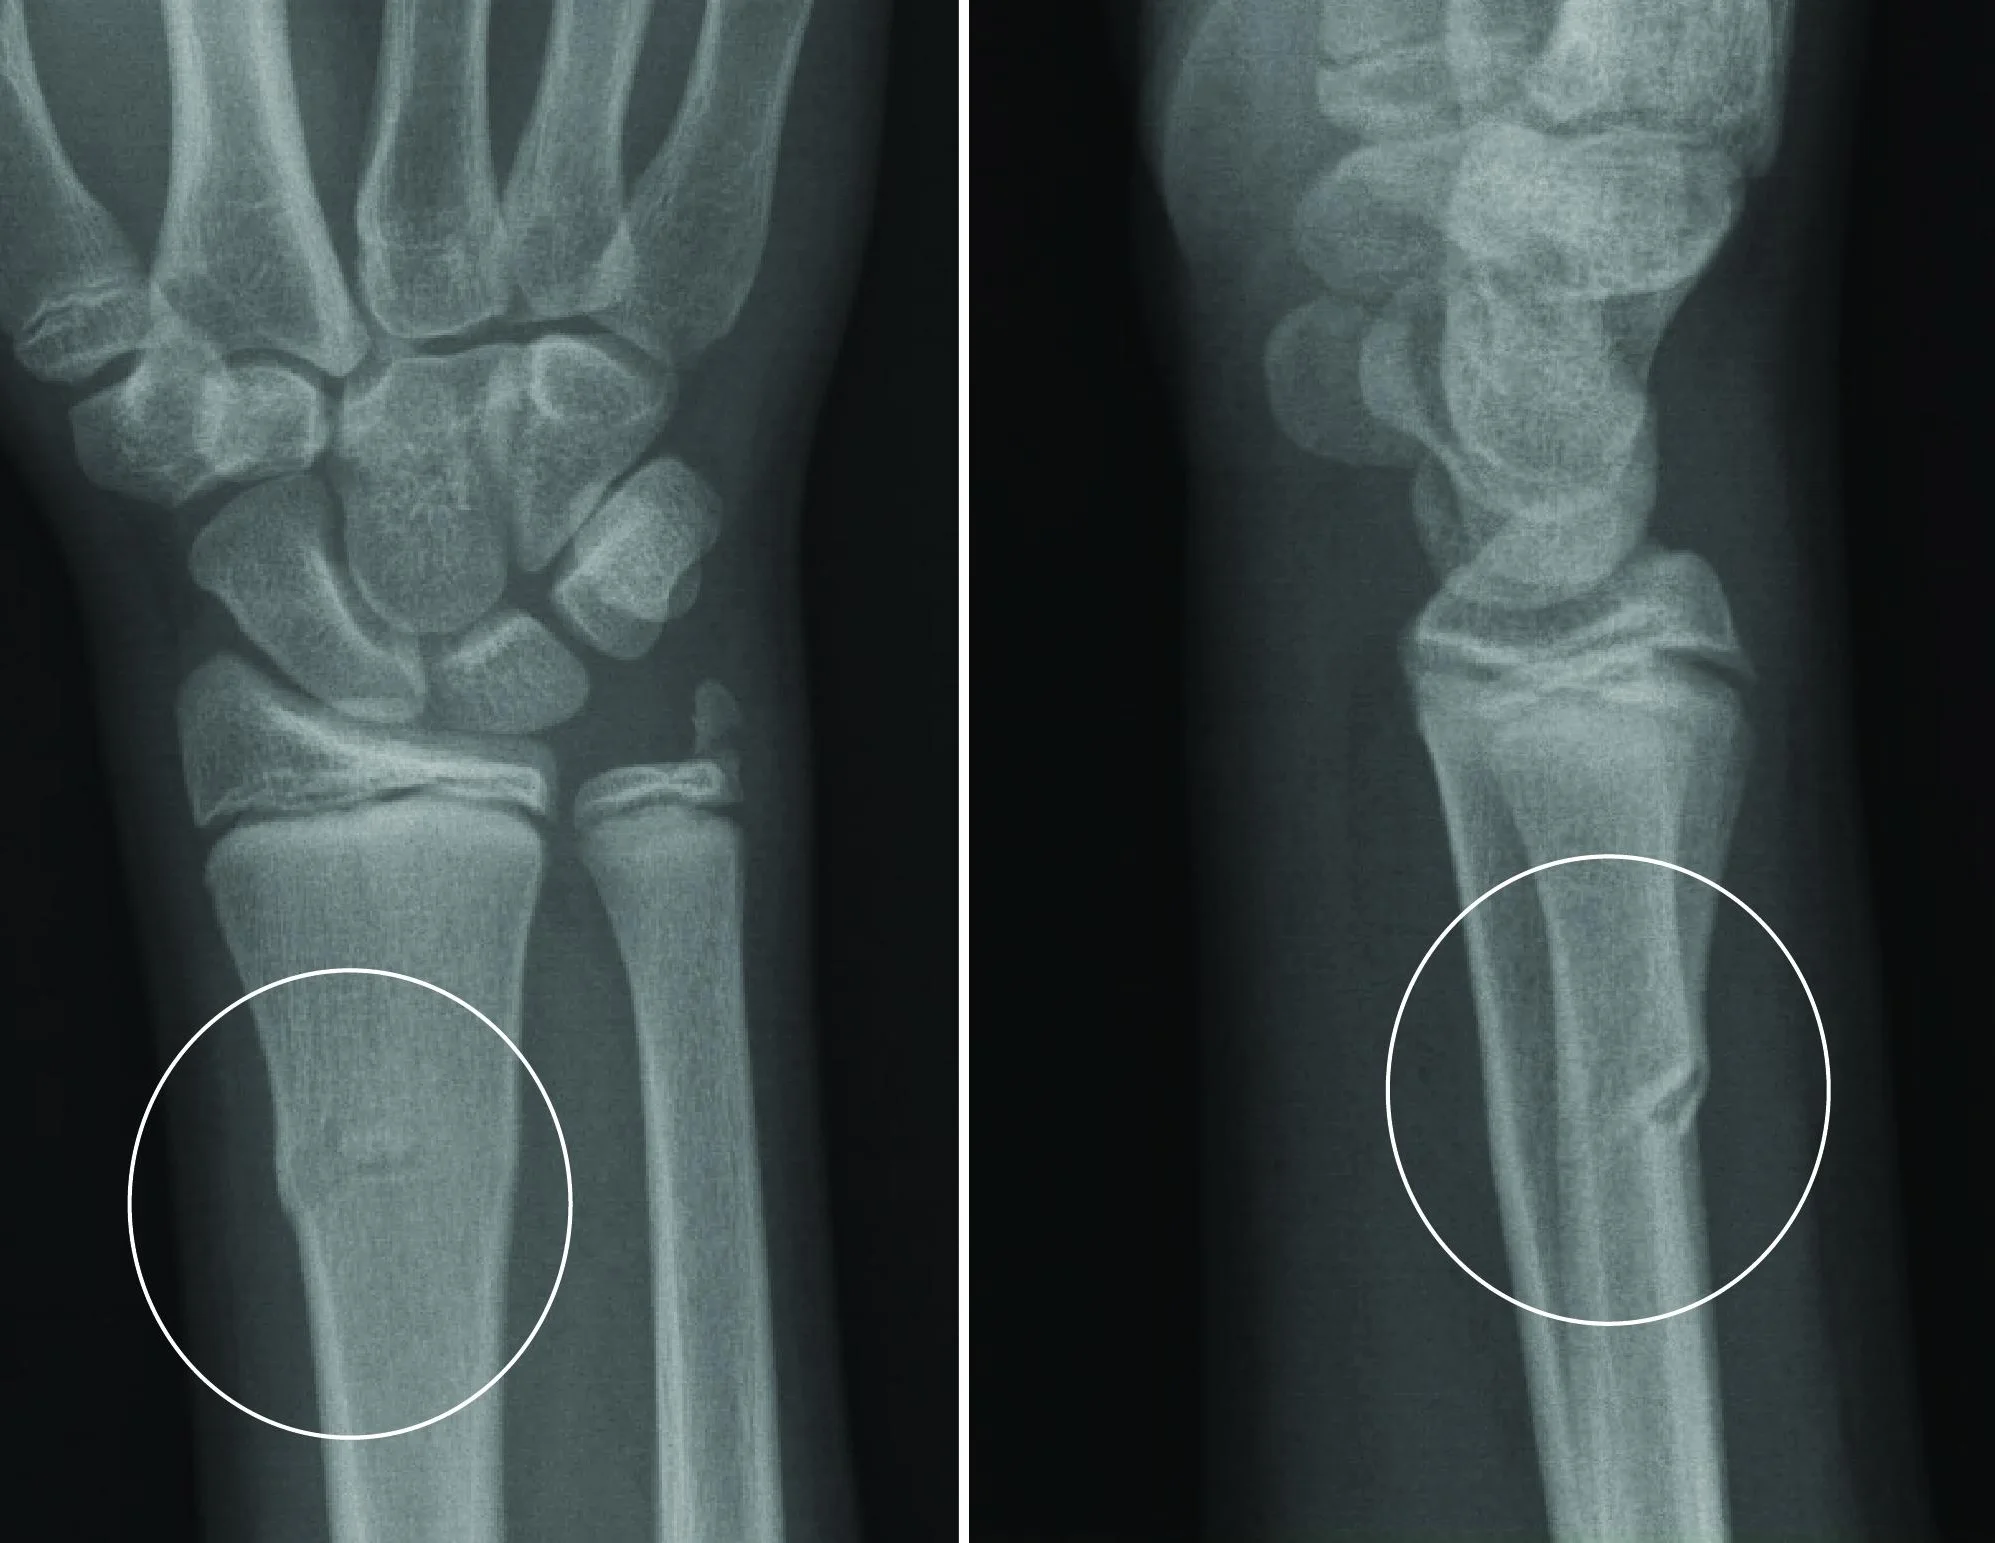

Buckle Fracture Raleigh Hand Surgery — Joseph J. Schreiber, MD

From www.clinicalguidelines.scot.nhs.uk

Buckle Fracture Raleigh Hand Surgery — Joseph J. Schreiber, MD Radius Bone Fracture Recovery Time Distal radius fractures can be reset either with surgery (open reduction) or without it (closed reduction). It can take anywhere from a few. Most distal radius fractures take about three months or more to heal before you can return to all activities. Even healthy bones near the wrist can suffer from a. Most distal radius fractures take 3 months or. Radius Bone Fracture Recovery Time.